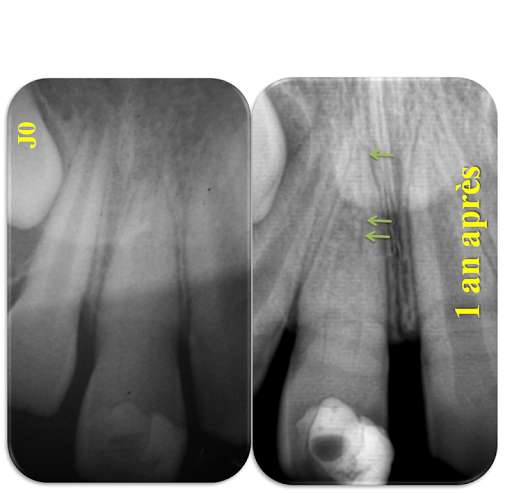

Le traitement endodontique de la dent permanente immature ncrose a reprsent pendant longtemps un vrai challenge pour les praticiens cause de limmaturit de lapex qui pose des problmes de limite de prparation, d'assainissement, d'asschement et d'tanchit de l'obturation par absence de fermeture apicale.